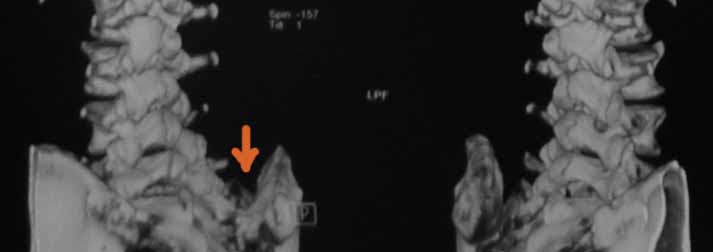

консультирована вертебролагами в разных НИИТО. В 2009г установлен диагноз - сакроилеит

справа. На представленных КТ имеется гипертрофия заднего отдела правой подвздошной кости с

образованием контакта с задней поверхностью крестца. В январе 2011 года выполнена попытка

операции положительного эффекта не получено. На контрольной КТ от 04.2011 обнаружено что,

желаемого результата операции не получено(интересующий участок удален частично), при

этом имеется расслоение заднего отдела правой подвздошной кости. Сейчас клиника таже